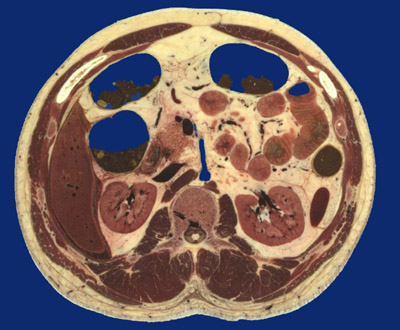

Identify the following regions in the image above: Rectus abdominus - Transversus abdominis - Intercostal m. - External oblique - Internal oblique - Latissimus dorsi - Sacrospinalis - Multifidus - Erector spinae m. - Psoas major - Uncinate process of pancreas - Transverse colon - Jejunum - Descending colon - Spleen tip - Left kidney - Right kidney - Crus of diaphragm - Liver - Descending aorta, superior mesenteric branch - Inferior vena cava - Superior mesenteric vein - Vertebral body - Conus medullaris